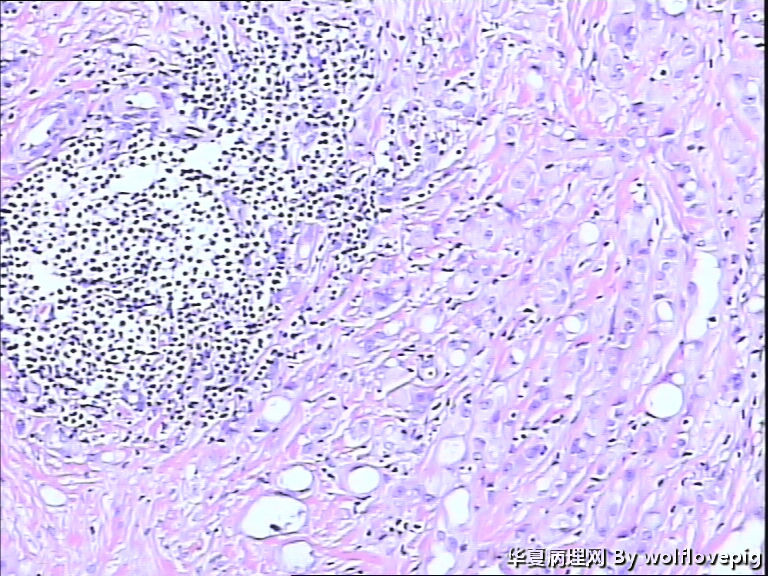

男,60y,左阴囊包块6月,位于附睾尾与睾丸之间,无粘连。灰白结节一个0.7*0.3*0.3,切面灰白、实体 、质韧。

图2

典型的腺瘤样瘤

同意腺瘤样瘤